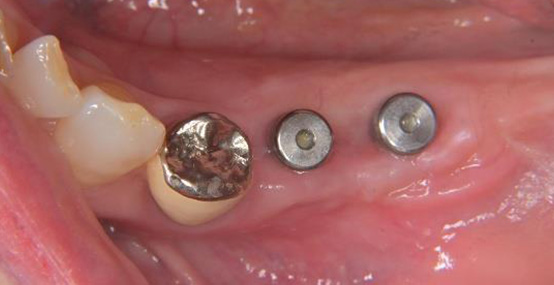

一次手術後(インプラント体埋入後の写真です)

インプラント手術後は大きなトラブルもなく、現在はしっかり咬めて違和感がない状態で経過しています。